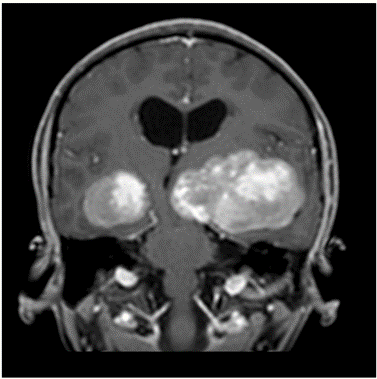

MRI outside hospital was done which was re-reported in our centre as Bilateral temporal lobe enhancing lesions. The left temporal lobe mass was larger in size and causing right-sided midline shift causing compression of the third ventricle with upstream hydrocephalus and transependymal seepage. These masses were reported as of neoplastic etiology, likely low-grade gliomas. Then MRI Brain with contrast was repeated which showed Bilateral intraventricular masses which are more or less stable in sizes causing hydrocephalus and compression effect at the level of the third ventricle towards the right side. Differentials included intraventricular tumors. No adjacent invasion is seen.

Figure 4: Lesion on T1 post contrast coronal brain MRI.

The mean age of onset with nodal disease is 20.6 years with a male to female ratio of 1.4:1 [6,17]. Patients who develop intracranial involvement, however, become symptomatic at a mean age of 34.9 years, with a strong male preponderance. In intracranial RDD, the most involved structures are the suprasellar region, cerebral convexity, parasagittal region, cavernous sinus, and petroclival region [18,19]. Radiologically, the typical MRI findings include isointense to hypointense T1-weighted signals and hyperintense T2-weighted signals with homogeneous enhancement post-contrast. Bitemporal lesions often exhibit a dural-based, meningioma-like appearance [20]. Intracranial RDD is commonly confused with meningioma and requires tumor histopathology and immunohistochemistry for its definitive diagnosis.

Bilateral temporal lobe involvement with mass effect, brainstem compression and obstruction of the ventricular system at the level of the third ventricle causing hydrocephalus is exceptional. Differential diagnosis includes several diseases (such as bilaterla glioma, PNET) in this case. A precise diagnosis could not be reached on clinical grounds alone.